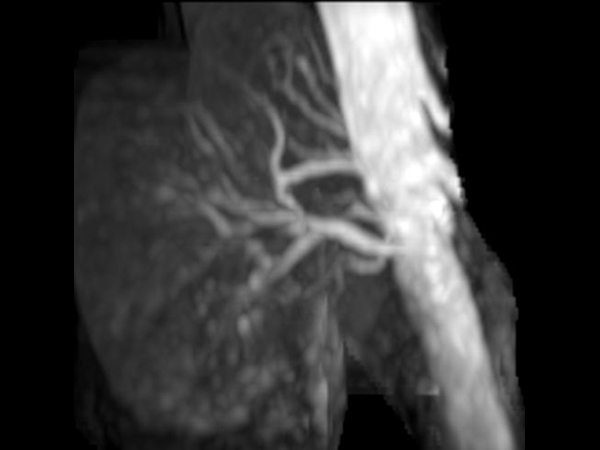

bTRANCE non-CE MRA (tumble)

-

bTRANCE non-CE MRA (spin)